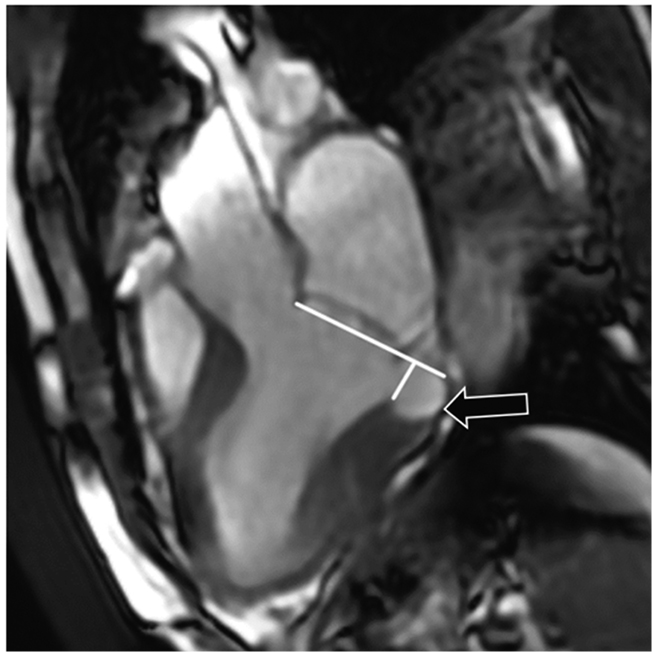

The distance from the base of the mitral valve fibrous annulus to the upper contour of the LV myocardium was measured on end-systolic cine images. The MAD extent at the level of the posterior and anterior mitral valve leaflets was measured along the three-chamber and long LV axis, respectively. The MAD extent was 11 mm and 5 mm unde the posterior and anterior leaflets, respectively (Fig. 5, 6).

Fig. 6. Left ventricular long axis (two chamber view), cine end-systolic image. Measurement of the mitral annular disjunction distance for the anterior mitral valve leaflet. Mitral annular disjunction is indicated by an arrow